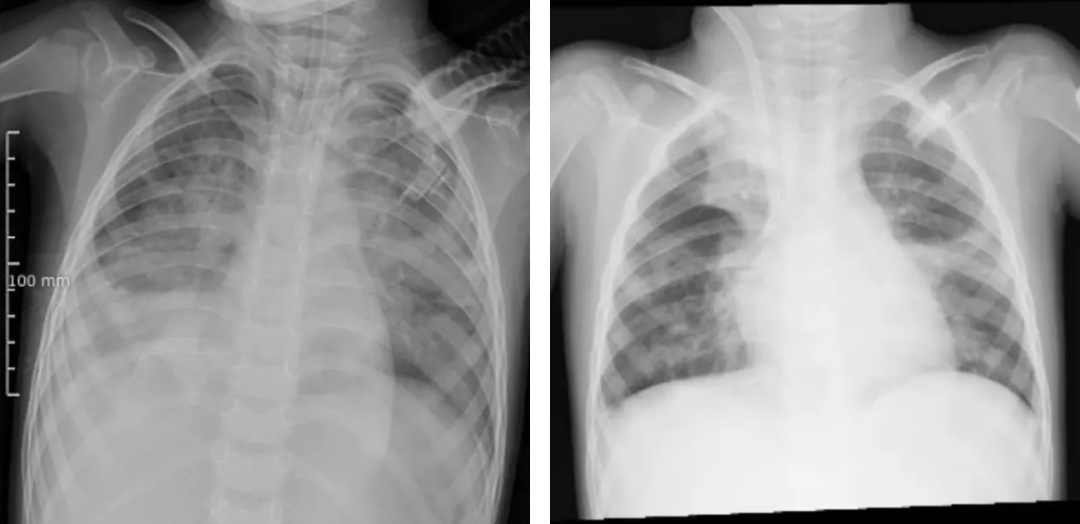

图源 河南省儿童医院(左图为ECMO上机前,肺部结构模糊,呈现“白肺”影像表现。右图为ECMO支持治疗5天后,肺部影像清晰度明显改善)